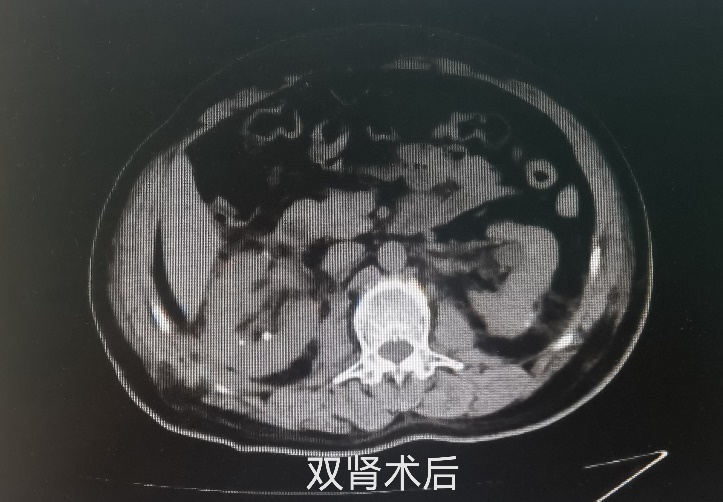

这次手术既是对外科医生技术的考验也是对心理素质的考验,手术操作要非常精细,既要切除肿瘤,又要尽可能多的保留正常肾组织,稍有不慎就可能伤及肾脏动脉导致大出血,那样最终只能将右肾切除。术中,张奇夫教授凭借丰富的经验及精湛的技术,剖开肾脏,将位于肾脏中央的肿瘤完整的剥离出来,成功为患者保住了右侧近90%肾组织,整个肾脏的阻断缺血时间只有26分钟,最大可能的减少了手术对肾脏功能的影响。保留肾脏的肿瘤切除手术就是与时间赛跑,因为在行肿瘤切除时需阻断肾脏的血流,要争取在最短时间内完成手术,以免肾脏功能因长时间缺血导致不可逆的损伤,术中还采用了肾脏表面低温技术,更有利于降低肾脏功能受损的风险。

最终,通过泌尿外科团队、手术室麻醉科及护理团队的密切配合,李大爷的手术获得了成功,为他保住了肾脏。术后复查肾功能血肌酐虽然有一过性的轻度升高,但是在3天之后恢复正常,未出现肾功能不全。